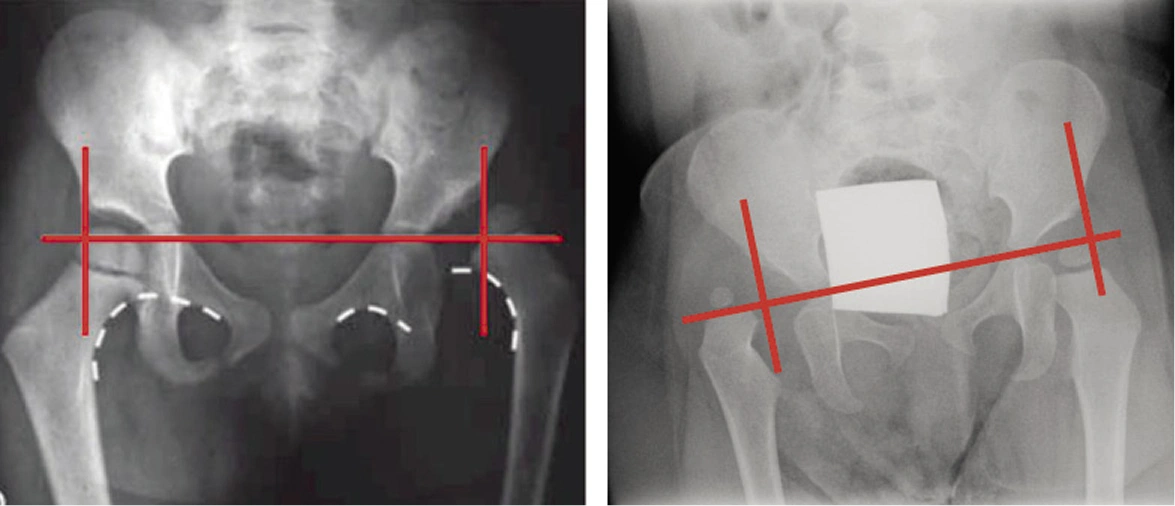

Diagnóstico y tratamiento especializado para la Displasia del Desarrollo de Cadera (DDC) en bebés y niños.

La DDC es una afección frecuente en la infancia que afecta la formación correcta de la articulación de la cadera. Si no se detecta y trata a tiempo, puede causar dolor, limitación funcional o requerir cirugía más adelante.

En nuestro centro, realizamos diagnósticos precisos con ultrasonido y seguimiento especializado para un desarrollo saludable.